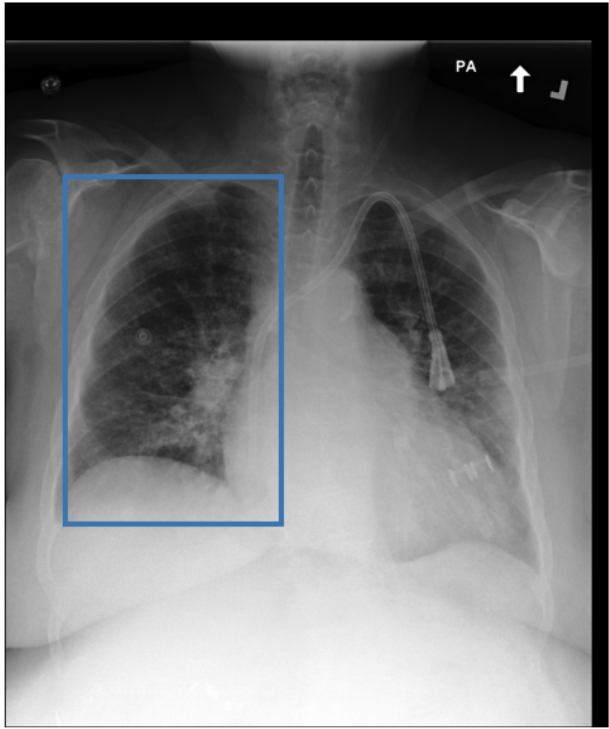

To address these drawbacks, state-of-the-art models such as MAIRA-2 [3] explicitly incorporate grounded report generation to better align local visual evidence with the textual findings. For example, MAIRA-2 is trained on a diverse set of localization-based tasks, including phrase grounding and grounded report generation. However, as shown in Figure 1, current models often exhibit a bias in which the target visual regions become overly associated with abnormal findings, leading to false positives in medical reports.

As shown in Table 1, our data composition reflects this imbalance: over 12.9M instances from Chest ImaGenome dominate the much smaller MS-CXR (815 PG instances) and PadChest-GR (12k instances) datasets. Beyond the imbalance between datasets, each dataset also exhibits substantial intra-dataset class imbalance. For example, anatomical regions in AGRG and semantic categories in PG are unevenly represented, leading the model to overfit frequent regions, neglect rare but clinically important ones, and hallucinate findings (Figure 1). Our curriculum framework addresses both sources of imbalance.

While MAIRA-2 exhibits a slightly lower hallucination rate for a few anatomies (e.g., ‘Cardiac Silhouette’), CURE consistently achieves a significantly lower contradiction rate and higher entailment rate across almost all categories. This improved performance likely stems from a key difference in the training data composition. Standard phrase grounding, used by MAIRA-2, is inherently biased towards abnormal findings. In contrast, our AGRG formulation exposes the model to both normal and abnormal descriptions for each anatomical region, leading to a more balanced and reliable generative process that mitigates the tendency to hallucinate abnormalities.